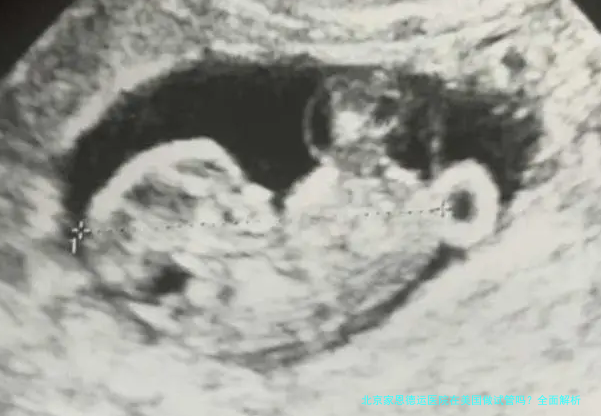

说到这儿,我想分享一个真实的案例。我认识一位叫小张的朋友,她和丈夫长期在美国工作,一直想尝试试管婴儿。最初,他们考虑在当地医院,但发现费用高昂且等待时间长。后来,通过朋友推荐,他们联系了北京家恩德运医院的国际部。医院安排了一次远程会诊,医生详细评估了他们的健康状况,并建议在美国完成基础检查后,再回国进行核心治疗。最终,小张夫妇顺利回国,在家恩德运医院完成了试管婴儿过程,并成功怀孕。这个案例让我深刻体会到,现代医疗已经打破了地域壁垒;虽然不能直接“在美国做试管”,但灵活的协作模式能有效解决问题。从个人观点出发,我认为家恩德运医院在生殖领域的专业性值得信赖,但跨境操作需要更多计划和沟通。如果你有类似需求,不妨主动联系医院,看看他们能提供哪些定制化方案。